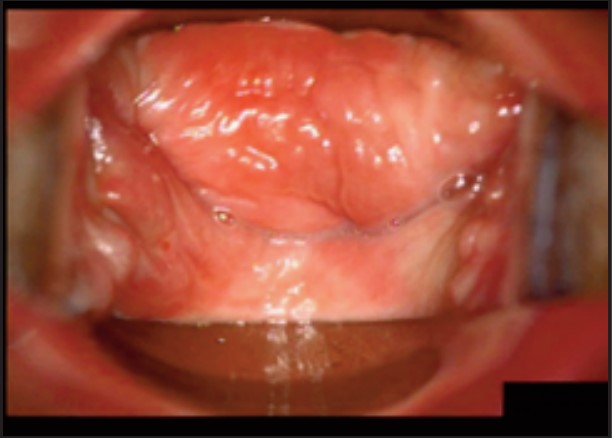

Під час спостереження до та після процедури, через 16 і 36 діб було зроблено вагінальні фотографії за допомогою Tele-Cervico (цервікографія) та виконано порівняння результатів до /після.

У пацієнток 1, 2 і 3 вагінальні складки утворилися та увиразнилися помітніше та сильніше, ніж вони були до лікування, ми оцінили цей клінічний результат після 1-го сеансу (через 16 діб). На нашу думку, такі виразні складки свідчать про підтяжку слизової оболонки піхви, що добре впливає на ущільнення піхви та проблему нетримання сечі. Через 36 діб після процедури ми спостерігали, що зруйнована анатомічна структура піхви відновила Н-подібну форму, тобто стала набагато здоровішою. Зокрема, у пацієнтки 4 структура піхви була цілковито зруйнована, стінки піхви обвисали через втрату еластичності. Однак через 36 днів після процедури структура піхви повністю відновила здорову Н-подібну форму [Див. Малюнок 3].

Пацієнтка №4

До

Після 36 діб

| Вік | 51 |

| Пологи | Природні. 2 хлопчики. |

| Лікування | 2 сеанси / 1 місяць |

| Огляд | 36 діб |

| Протокол | 1 сеанс – 440 імпульсів 2 сеанс – 200 імпульсів |

| Результати | √ Істотне відновлення H-подібної структури √ Зменшилася секреція √ Підтяжка |